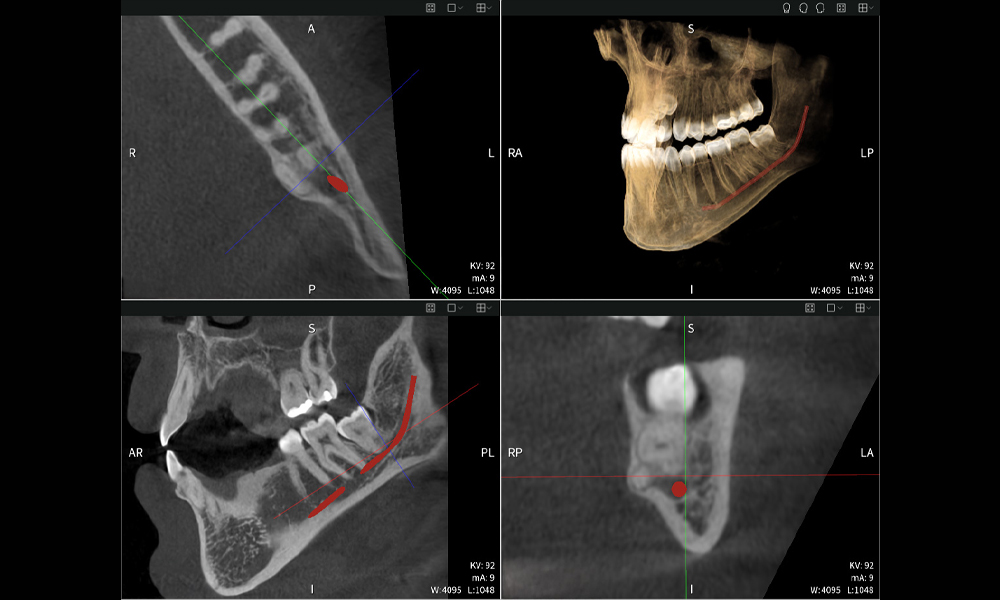

Nachstehend finden Sie einen Fall von Dr. med. dent. Oliver A. Centrella, in dem die CBCT-Aufnahmen mit Seethrough Max entscheidende Informationen zur komplexen Anatomie sowie zur kritischen Beziehung zwischen den Weisheitszähnen und dem Nervus alveolaris inferior lieferten. Bei diesem Fall besteht eine Indikation zur chirurgischen Entfernung der Weisheitszähne.

Abbildung a: Bildgebungsergebnisse von Seethrough Max vor einem schwarzen Hintergrund.

Abbildung a

• Oben links: Axiale Schnittansicht des linken Unterkiefers (Region 38) mit Darstellung des Nervus alveolaris inferior (rot) in unmittelbarer Nähe zu den Wurzeln des Zahns 38.

• Oben rechts: 3D-Rekonstruktion des gesamten Unterkiefers zur Orientierung. Der rot markierte Nervus alveolaris inferior verdeutlicht seine Lage im Kieferknochen.

• Unten links: Sagittale Ansicht des Unterkiefers (Region 38), die die enge räumliche Beziehung zwischen den Wurzeln und dem Nervenkanal verdeutlicht.

• Unten rechts: Koronale Ansicht des Unterkiefers (Region 38) entscheidend für die Beurteilung der räumlichen Lage der Wurzeln zum Nerven.